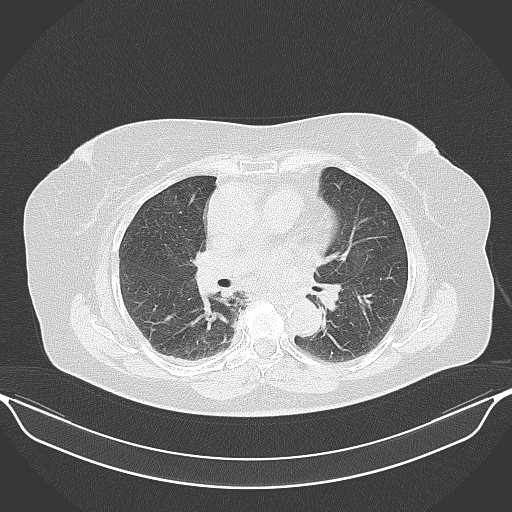

Original NATIVE CT scan (input)

No window - Raw intensity values

Lung window (WL -600, WW 1500 β†’ Low βˆ’1350, High +150)

Mediastinum window (WL 40, WW 400 β†’ Low βˆ’160, High +240)